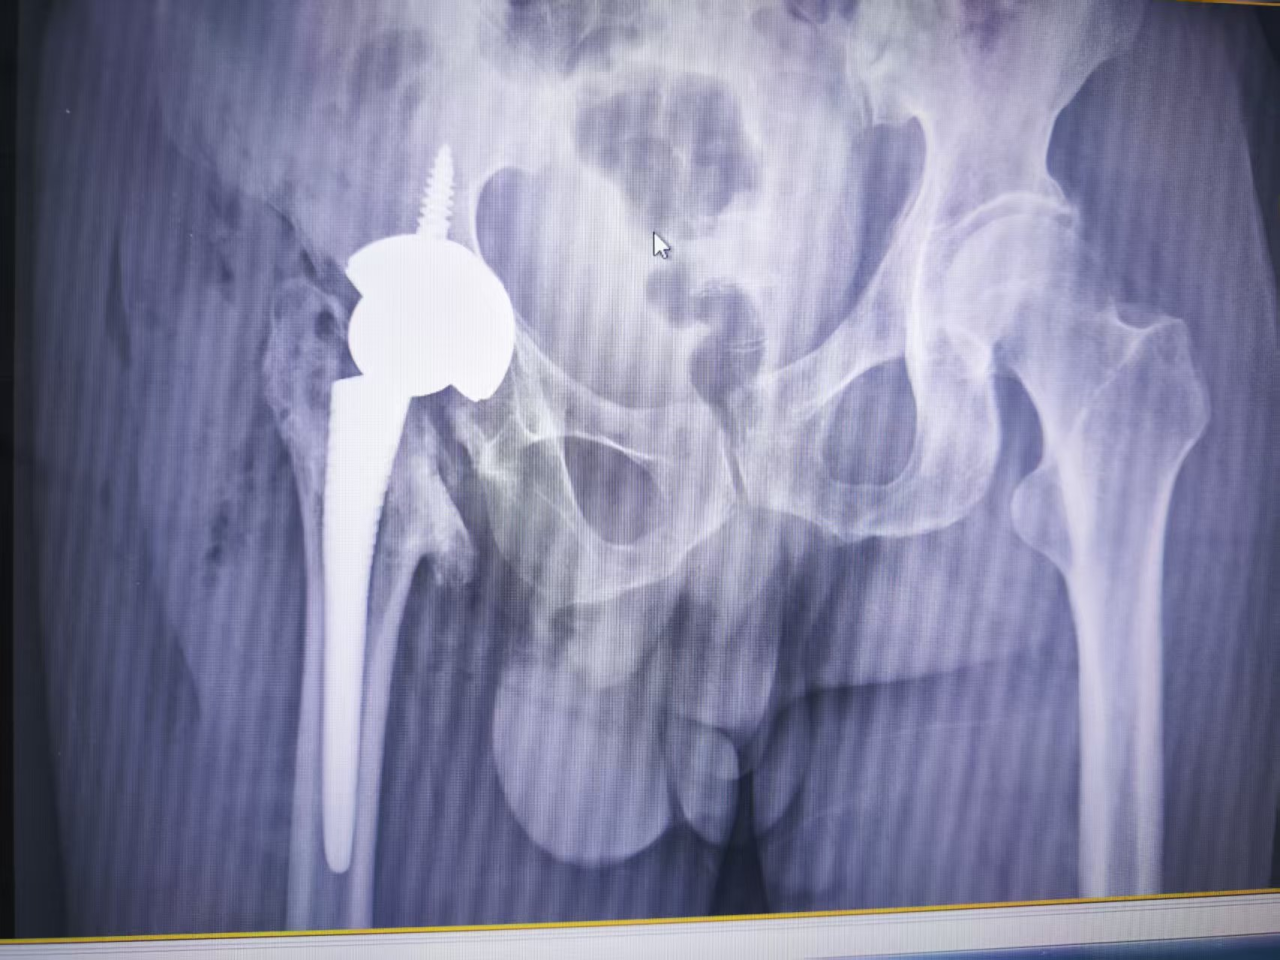

手术过程中,骨科团队全神贯注,先清除病变组织,重塑髋臼“骨窝”;接着精准植入人工关节,调整双腿长度;下移大结节,恢复肌肉发力点。术中出血仅300毫升,未输血。

术后次日,种先生疼痛大减。第二天,在医护人员的协助下,他借助助行器迈出第一步,激动地说:“腿终于听使唤了!这么多年了,我终于又能好好走路了!”复查显示人工关节位置精准,双腿等长,手术成功。